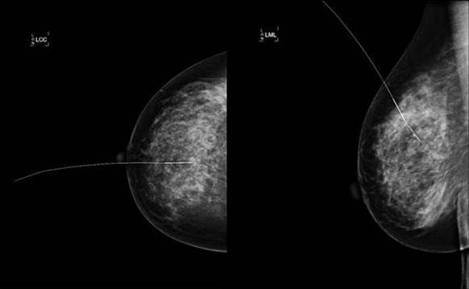

Es realitza una projecció mamogrà fica crani - caudal i lateral a 90º de la mama amb l’arpo.

Apòsit estèril sobre la zona amb fixació externa de l’arpó amb tires de sutura (cal tenir en compte que la pacient a de portar l’apòsit a quiròfan).

Remetre la pacient amb tots els estudis radiològics a la planta d’hospitalització.